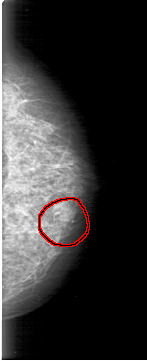

FILE: D_4038_1.LEFT_MLO.OVERLAY

TOTAL_ABNORMALITIES 1

ABNORMALITY 1

LESION_TYPE MASS SHAPE OVAL MARGINS OBSCURED

ASSESSMENT 0

SUBTLETY 4

PATHOLOGY BENIGN

TOTAL_OUTLINES 1

BOUNDARY